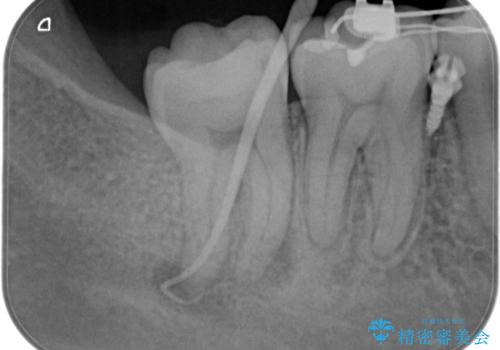

- 奥の歯茎にニキビみたいなものができたことを主訴に来院されました。

来院時は特に痛みはありませんでしたが、5年ほど前は痛みがあり、他院で虫歯の治療をしたことがあるとのことでした。

歯髄検査をし、歯髄壊死と診断できたため治療を介入しています。

咬合面の修復材料を除去すると内部に細菌の塊である多量のカリエスが残存しており、それが原因で歯髄が壊死したと考えられます。

治療中、細菌の除去を徹底的に行えるように顕微鏡とラバーダム(ゴムのシート)を用いて行いました。